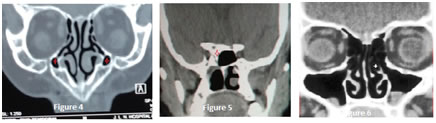

Figure 4                                     Figure 5                                                Figure 6

Figure 1: Bilateral paradoxical middle turbinate (white star) and Left Haller cell (red star); Figure 2: Bilateral Haller cells (white star) and Right side Prominent Bulla Ethmoidalis (Red star); Figure 3: Right side Onodi cell; Figure 4: Bilateral Maxillary Hypoplasia; Figure 5: Right Sphenoid aplasia; Figure 6: Left Uncinate process pneumatisation